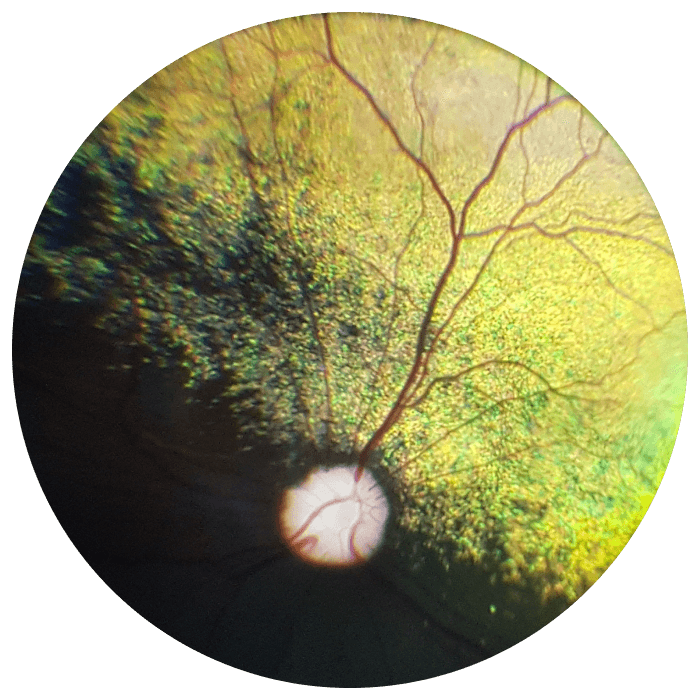

American Shorthair

OD, Normal